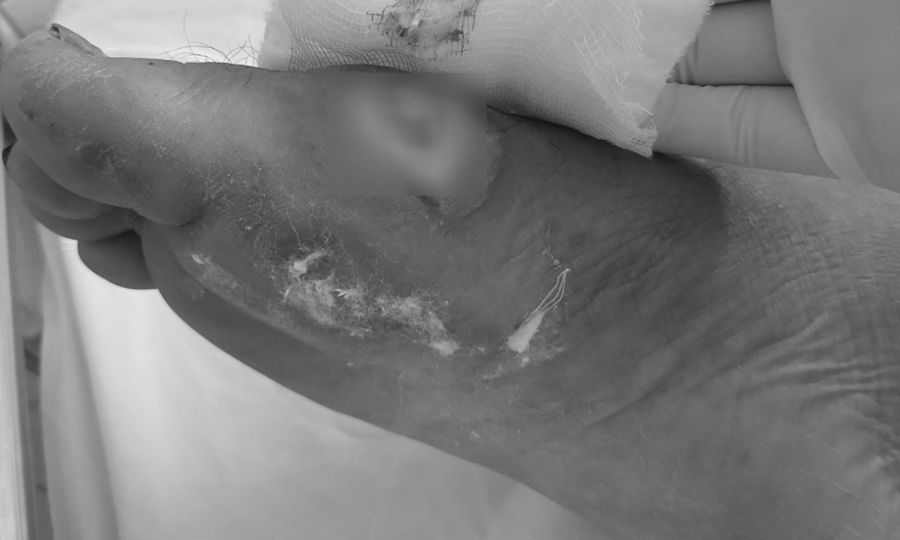

Chân bệnh nhân bị hoại tử do vi khuẩn Burkholderia. Ảnh: Bệnh viện cung cấp.

Sau đợt bão lũ kéo dài từ đầu tháng 10 đến nay, số ca nhiễm bệnh Whitmore ở nhiều tỉnh miền Trung ngày càng gia tăng. Quảng Trị ghi nhận 24 trường hợp, Bệnh viện Thừa Thiên-Huế tiếp nhận 30 trường hợp … Bệnh viện Đà Nẵng điều trị 29 trường hợp, bệnh nhân chủ yếu đến từ Quảng Nam, Nghệ An, Quảng Ngãi và Đà Nẵng. – Vết thương do áp xe do Whitmore gây ra đã được điều trị. Ảnh: Bệnh viện cung cấp.